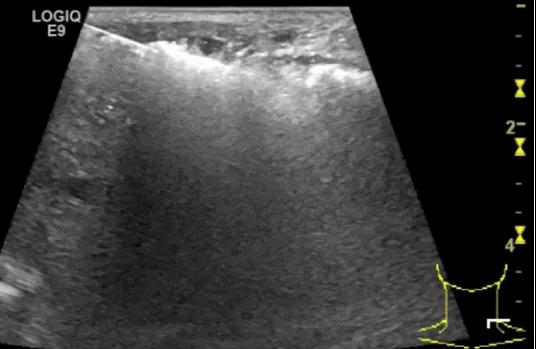

第三例是甲状腺癌患者,双侧甲状腺癌切除术后、碘治疗后一年余效果欠佳,超声显示左颈3区3枚低回声结节,穿刺示甲状腺乳头状癌转移。患者不愿意手术,希望采取局部治疗。对病灶进行液体隔离后采取热消融术,由于淋巴结较小,热消融一分钟左右完全灭活,术后增强影像显示没有脏器充填。

(病例3图例)